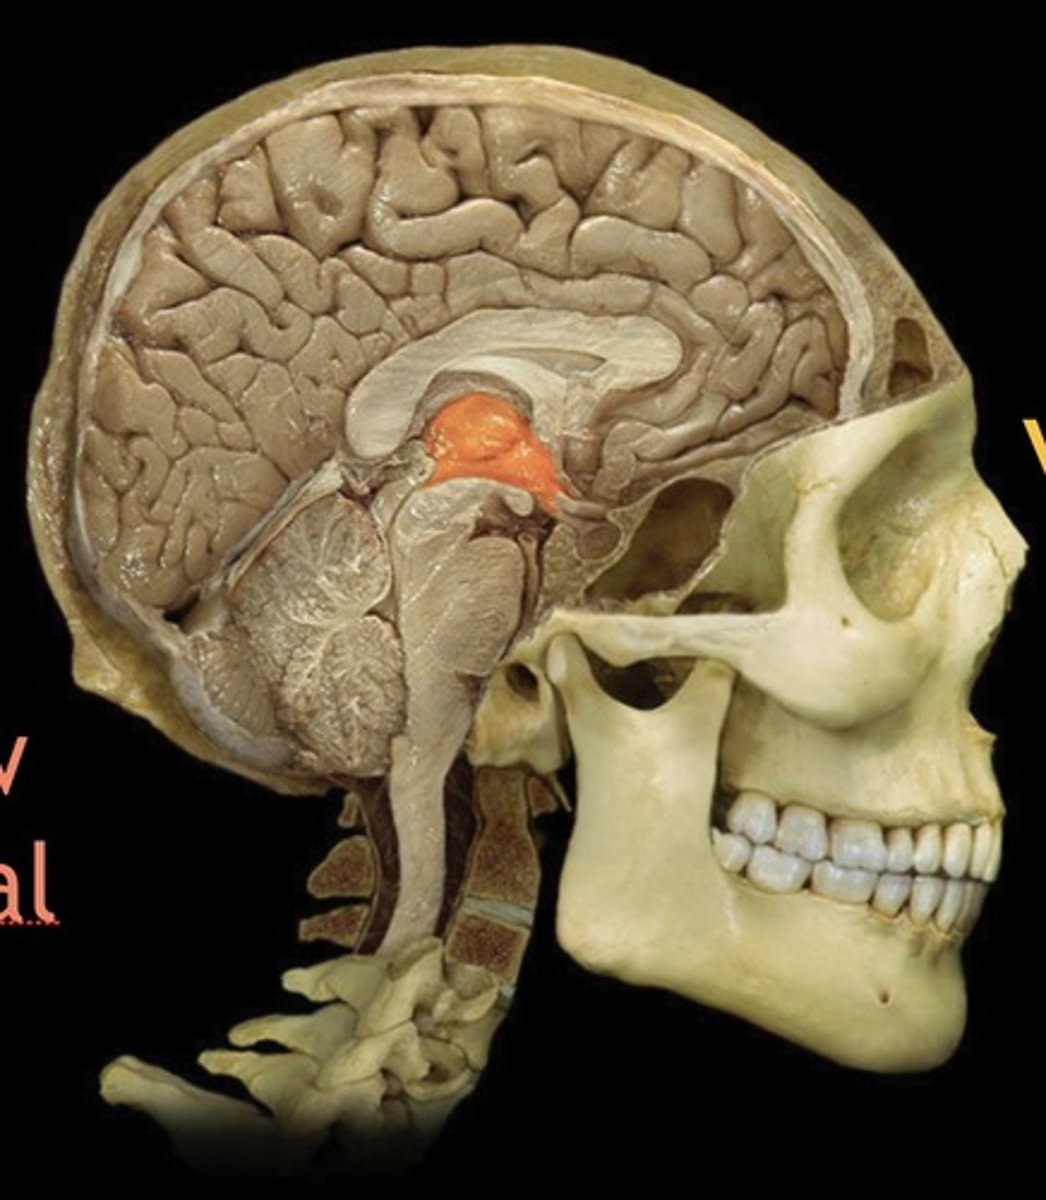

Thalamus

Name this structure

Hypothalamus

Name this structure

Pineal gland

Name this structure

Mamillary Body

Name this structure

Pituitary gland

Name this structure

Third Ventricle

Name this structure